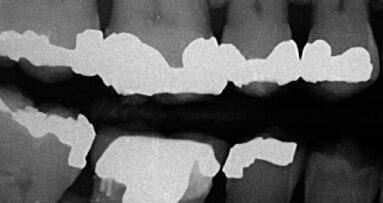

Si effettuano gli esami radiografici di controllo dai quali si evidenziano i segnali della guarigione. L’aspetto clinico dei tessuti nella zona della pre-maxilla evidenzia l’entità della ricostruzione effettuata. La guarigione ha portato la mucosa alveolare in cresta e quindi è fondamentale conservare un’adeguata quantità di gengiva aderente. È necessario anche in questa fase decidere la linea dell’incisione primaria; l’incisione fatta conserva parte della gengiva aderente nella porzione vestibolare del lembo primario. Si rimuovono le viti di fissaggio e poi si procede a separare le due porzioni della griglia, quella vestibolare e quella palatale attraverso una leva in corrispondenza dell’esclusiva linea di separazione disegnata nella griglia (Fig. 19). Quello che appare subito è l’eccellente rigenerazione ottenuta e la ricostruzione della forma ad arco originale dell’arcata (Fig 20). Se confrontiamo la situazione critica di partenza a quella finale evidenziamo l’entità della ricostruzione ottenuta (Figg. 21-24).

La valutazione clinica dell’eccellente aspetto dell’osso neoformato deve però avere anche un riscontro istologico. Per questo, ma anche per decidere il timing successivo del posizionamento implantare, decidiamo di eseguire delle carote nei siti di successivo posizionamento implantare per effettuare l’esame istomorfometrico che conferma un’ottima qualità dell’osso neoformato (Fig. 25); l’osso infatti presenta normale morfologia, caratterizzata da trabecole ossee neoformate che vanno a delimitare ampi spazi midollari ricchi di vasi. La vascolarizzazione si presenta in entrambi i siti sotto forma di vasi sanguigni dall’ampio lume distribuiti in gruppi di 5-7 (Figg. 26, 27). Si notano osteociti di grandi dimensioni e alcuni osteoblasti in fase attiva di deposizione di matrice osteoide (Figg. 28, 29). Non si riscontrano cellule osteoclastiche, segno che il rimodellamento risulta minimo e indice quindi del fatto che l’osso si trova in uno stadio avanzato di organizzazione e maturazione (Figg. 30-32).